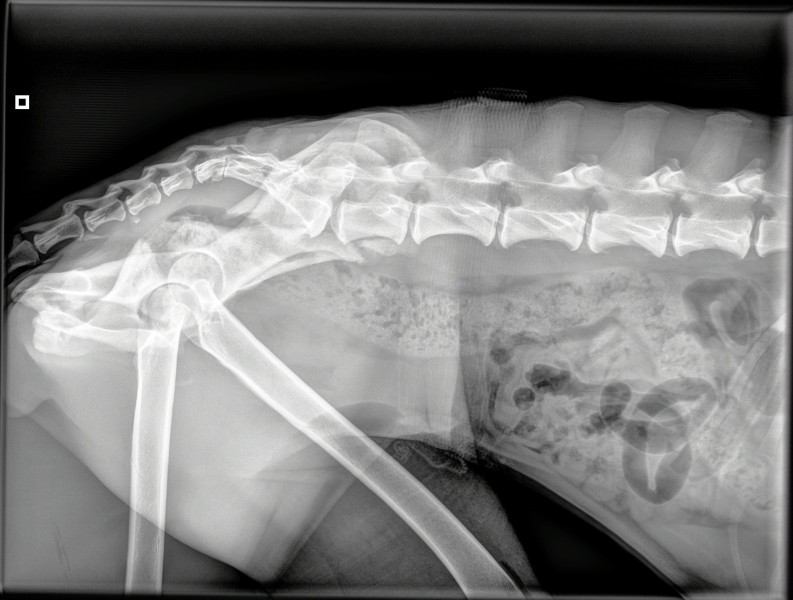

L’intervention sur le bassin de Mel a été une réussite, le chirurgien a atteint ses objectifs :

redresser le bassin, réaligner les abouts osseux fracturés puis stabiliser au moyen d’une

plaque avec vis qu’elle gardera à vie si elle le supporte bien.

Une radiographie de contrôle aura lieu dans 7-8 semaines ; durant ce temps, pas de course,

pas de saut et des sorties en laisse puis sera mis en place un programme de physiothérapie ;

Regardez sur les photos jointes, son bassin avant et après….

AVANT

APRES